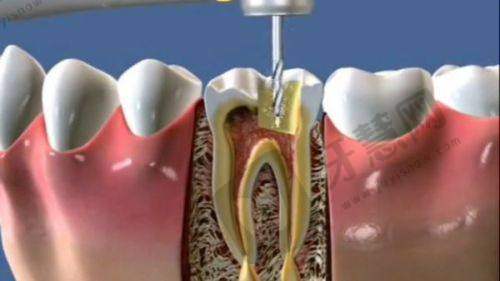

特色项目优势:北京欢乐将臣口腔门诊部的特色项目丰富多样。牙齿修复项目采用精良材料和技术,能根据患者不同牙齿情况进行个性化修复。例如种植牙修复,稳定性高、舒适度好,几乎与真牙无异,有效修复牙齿咀嚼功能。牙齿美白项目采用安心效率高美白技术,短时间内显著提升牙齿洁白度,且对牙齿损伤小。正畸项目方面,医生会根据患者牙齿畸形程度制定专属矫正方案,传统金属牙套矫正和隐形矫正都能达到理想成效,隐形矫正更因美观、舒适、可自行摘戴等优势受到特别多患者青睐,为患者带来良好的口腔诊疗体验。

收费合理性与透明性:北京欢乐将臣口腔门诊部的收费价格合理透明。牙齿修复价格:普通烤瓷牙修复一颗的价格在800 - 1500元左右,全瓷牙修复一颗的价格在2000 - 3500元左右。种植牙价格因种植体品牌不同而有差异,一般单颗种植牙价格在8000 - 15000元之间。牙齿美白价格:冷光美白一次的价格在1200 - 2000元左右。正畸项目价格:传统金属牙套矫正的费用在8000 - 15000元,隐形矫正的费用相对较高,在20000 - 35000元左右。门诊部会根据患者具体情况和治疗方案详细说明费用,让患者清楚了解每一项收费用途。